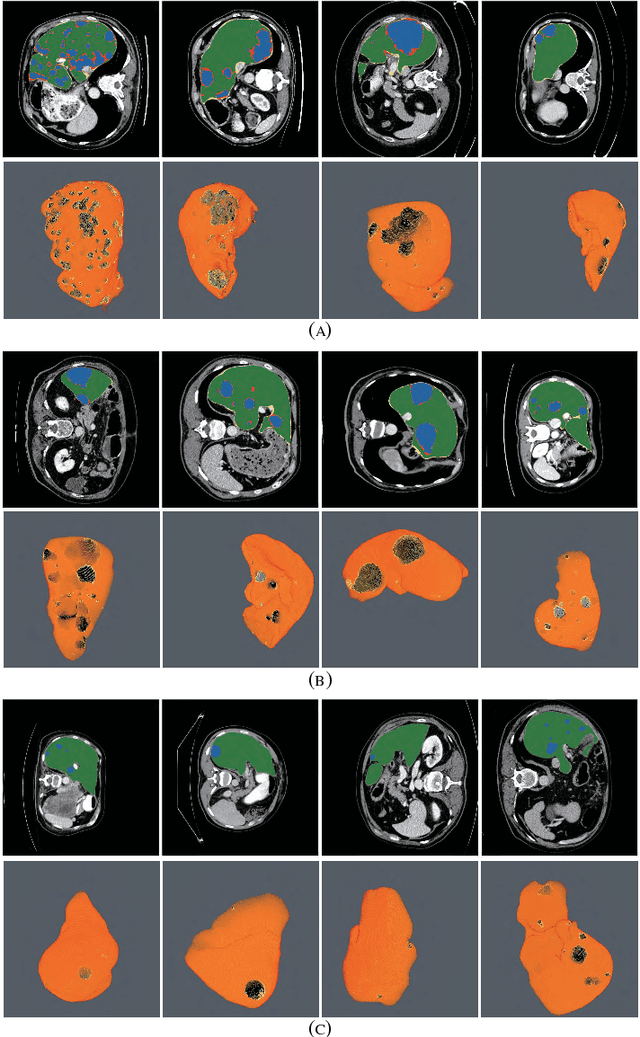

Abstract:The insufficiency of annotated medical imaging scans for cancer makes it challenging to train and validate data-hungry deep learning models in precision oncology. We propose a new richer generative adversarial network for free-form 3D tumor/lesion synthesis in computed tomography (CT) images. The network is composed of a new richer convolutional feature enhanced dilated-gated generator (RicherDG) and a hybrid loss function. The RicherDG has dilated-gated convolution layers to enable tumor-painting and to enlarge perceptive fields; and it has a novel richer convolutional feature association branch to recover multi-scale convolutional features especially from uncertain boundaries between tumor and surrounding healthy tissues. The hybrid loss function, which consists of a diverse range of losses, is designed to aggregate complementary information to improve optimization. We perform a comprehensive evaluation of the synthesis results on a wide range of public CT image datasets covering the liver, kidney tumors, and lung nodules. The qualitative and quantitative evaluations and ablation study demonstrated improved synthesizing results over advanced tumor synthesis methods.